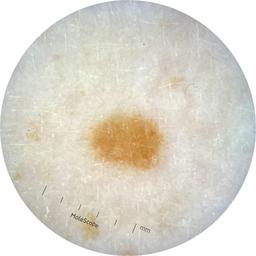

ISIC_9785574

Information

2003 x 2003

Attribute to

MEL-SELF Trial, https://www.sydney.edu.au/medicine-health/our-research/research-centres/melself-project.html

License

Clinical

Field Value

acquisition_day 148

age_approx 45

anatom_site_1 Head and neck

anatom_site_general head/neck

concomitant_biopsy False

diagnosis_1 Benign

diagnosis_confirm_type single image expert consensus

family_hx_mm True

image_manipulation instrument only

image_type dermoscopic

lesion_id IL_0236417

patient_id IP_8456088

personal_hx_mm True

sex female